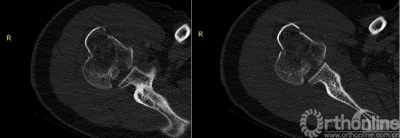

2.肩关节CT

确定肩关节后脱位。

了解反Hill-sachs损伤和程度。

观察肱骨近端主要骨折线和次要骨折线及形态。